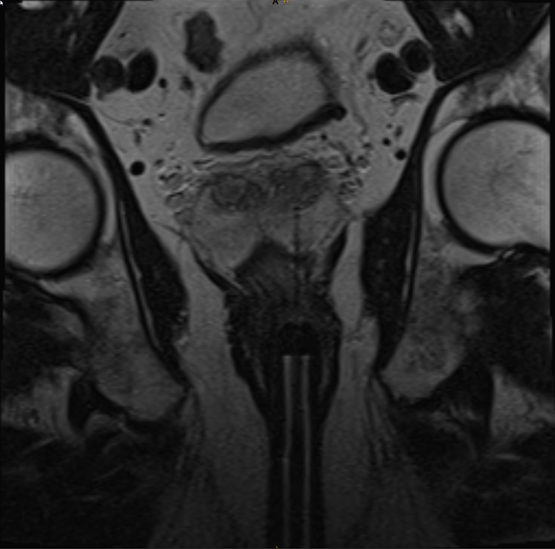

Prostata-Magnetresonanztomografie (Prostata-MRT)

Durch ein multiparametrisches Prostata-MRT entdeckter Prostatakrebs in der Radiologie Nürnberg.

Wer führt das Prostata-MRT durch?

Der Chefarzt der Radiologie Nürnberg, Professor Dr. med. Wolfgang Wüst, und sein Oberarztteam verfügen über die höchste in Deutschland erreichbare Qualifikationsstufe für das Prostata-MRT: das Q2-Zertifikat der Deutschen Röntgengesellschaft für mpMRT Prostata.

Wie funktioniert die multiparametrische Prostata-MRT?

Das Prostatakarzinom ist mit jährlich rund 50.000 Neuerkrankungen in Deutschland die häufigste bösartige Tumorerkrankung bei Männern. Wie bei vielen bösartigen Tumorerkrankungen ist es im Frühstadium meist symptomlos und wird deshalb oft erst spät entdeckt.

Bei rund 30 Prozent der über 50-jährigen Männer und bis zu 70 Prozent der 80-jährigen Männer findet sich ein symptomloses Prostatakarzinom. Aufgrund dieser Zahlen ist eine frühzeitige Erkennung des Tumors essentiell.

Dabei spielt die multiparametrische Prostata-MRT die zentrale Rolle und ist herkömmlichen Vorsorgemethoden wie dem Tastbefund, der Ultraschalluntersuchung oder der Bestimmung des Prostata-spezifischen Antigens (PSA-Wert) aus einer Blutprobe überlegen.

Bei der Prostata-Magnetresonanztomografie kommen verschiedene Techniken zur Darstellung der Anatomie, der Zelldichte und der Gefäßversorgung der Prostata zum Einsatz. Die Prostata-MRT gilt daher zurzeit als das sensitivste radiologische Verfahren einen Tumor zu entdecken, wobei ein unauffälliges MRT die Erkrankung mit hoher Sicherheit ausschließt. Dadurch können eventuell unnötige diagnostische und therapeutische Eingriffe verhindert werden.

Die Prostata-MRT ist eine aufwändige und technisch anspruchsvolle Untersuchung und liefert nur in der Hand von Experten verlässliche und reproduzierbare Ergebnisse. Wichtig ist der Einsatz moderner Techniken, wie sie von den Fachgesellschaften für Urologie und Uroradiologie im Rahmen der sogenannten multiparametrischen MRT (mpMRT) gefordert werden. Die Begutachtung erfolgt gemäß der sogenannten PI-RADS-Kriterien („Prostate Imaging Reporting and Data System") in ihrer aktuellen Version.